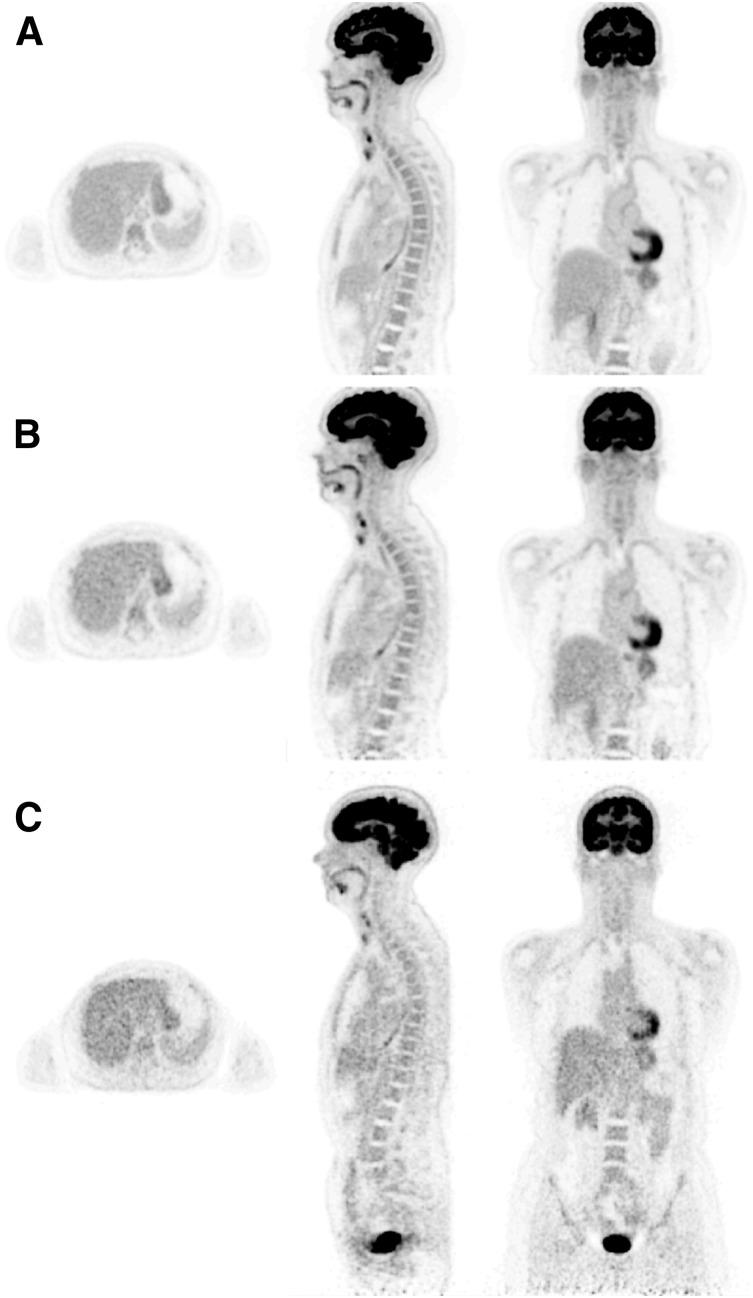

We report on the development of the PennPET Explorer whole-body imager. The PennPET Explorer is a multiring system designed with a long axial field of view. The imager is scalable and comprises multiple 22.9-cm-long ring segments, each with 18 detector modules based on a commercial digital silicon photomultiplier. A prototype 3-segment imager has been completed and tested with an active 64-cm axial field of view. The instrument design is described, and its physical performance measurements are presented. These include sensitivity of 55 kcps/MBq, spatial resolution of 4.0 mm, energy resolution of 12%, timing resolution of 256 ps, and a noise-equivalent count rate above 1,000 kcps beyond 30 kBq/mL. After an evaluation of lesion torso phantoms to characterize quantitative accuracy, human studies were performed on healthy volunteers. The physical performance measurements validated the system design and led to high-quality human studies.

我们报告了 PennPET Explorer 全身成像仪的开发情况。PennPET Explorer 是一款多环系统,设计具有长轴向视野。该成像仪具有可扩展性,由多个 22.9 厘米长的环段组成,每个环段都有 18 个基于商用数字硅光电倍增管的探测器模块。已经完成了一个具有主动 64 厘米轴向视野的 3 段式原型机,并进行了测试。本文描述了仪器的设计,并介绍了其物理性能测量结果。这些结果包括 55 kcps/MBq 的灵敏度、4.0 毫米的空间分辨率、12%的能量分辨率、256 ps 的时间分辨率以及在 30 kBq/mL 以上超过 1000 kcps 的噪声等效计数率。在对用于定量准确性评估的病灶体模进行评估后,我们在健康志愿者中进行了人体研究。物理性能测量验证了系统设计,并实现了高质量的人体研究。